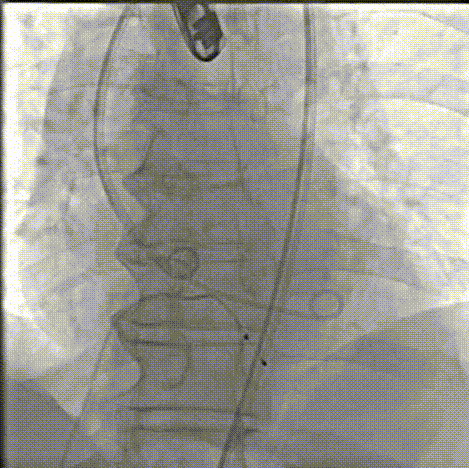

主动脉根部造影轻中度反流

20mm球囊预扩,有腰无漏,冠脉显影良好